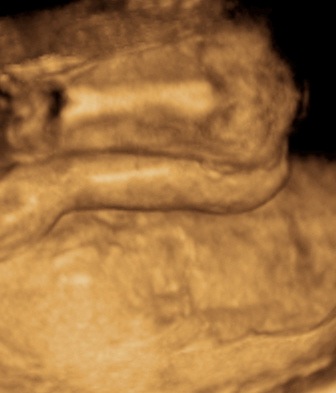

A 3D-s babafotok meg mindig lenyugoznek, nem birok betelni veluk. SZomoruan olvasom, hogy mennyi aprobb-nagyobb kellemetlensegetek van, de szerintem mindenki nagyon szuperul halad, ugyesek vagytok...le a kalappal foleg a dolgozok, vagy mar babasok elott! majd most teszek fel kepeket es is Azzurrarol, bar mar tobb, mint 5 hete keszultek, de ujabbak mar nem lesznek, es mivel kimaradtam abban az idoszakban, most potolom. Az tuti, hogy ezentul mindenkinek javasolni fogom a 4D-t ilyen koran is (22+1 hetesen voltunk), mert bar csimota ducibb volt az atlagnal es mar akkor volt rajta jo adagnyi izom (ez is a napi 1 l tej

), de egy sovanyabb baba is csodaszep szerintem...mindent el lehet mondani, csak azt nem, hogy csontkollekciok lennenek. Osszessegeben ugy nez ki, hogy ram hasonlit, de a szemoldokcsontja es a szaja az egy az egyben a parome...szerencsere...neki az sokkal szebb...remelem, haj-ugyben is ra ut majd